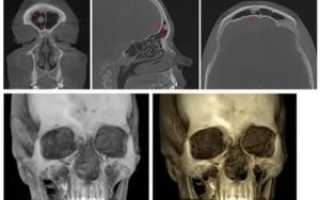

Рентген осуществляется в двух проекциях. Позволяет установить имеющиеся разрушения кости, а также выявить наличие плотного и губчатого образования за ее пределами. В том случае, когда опухоль имеет незначительные размеры, рентгенография оказывается малоэффективной.

Для постановки точного диагноза могут быть использованы дополнительные диагностические методы.

Позволяет установить, какие новообразование имеет размеры, а также определяет точное место его формирования. Кроме того, при помощи КТ становится возможным определение степени однородности нароста.

Благодаря такому исследованию специалисты могут выявить, к какому типу относится опухоль. Также методика позволяет визуализировать структуру тканей.

Наибольшая эффективность данного способа диагностики отмечается при развитии гетеропластической остеомы лобной пазухи.

Основной диагностической процедурой считается рентгенография, при которой в области поражения идентифицируется равномерное затемнение с нечеткими краями.

Для выяснения точного расположения опухоли, как правило, осуществляется серия рентгеновских снимков под разным углом.

Основной способ диагностики – рентгенография. На снимке это будет выглядеть как однородная по структуре округлая опухоль с четкими границами. Остеоидная остеома на снимке представляет собой нечеткий дефект – очаг деструкции.

- Рентгенография позволяет узнать: месторасположение остеомы в кости, строение опухоле, степень деструкции кости, на которой находится новообразование, – а также определить, единичная опухоль или это множественное разрастание.

- При очень маленьких остеомах рентгенография не информативна, поэтому проводится компьютерная томография, позволяющая визуализировать малейшие детали структуры опухоли и замерить размеры деструкции.

диагностические снимки остеом черепа

Основным методом, позволяющим обнаружить любую опухоль кости, в том числе, остеому, является рентгенография. Если новообразование расположено глубоко в тканях головы, имеет небольшой размер, поражает кости черепа с внутренней стороны, то целесообразнее произвести компьютерную томографию, дающую больший объем информации относительно его размеров и месторасположения.